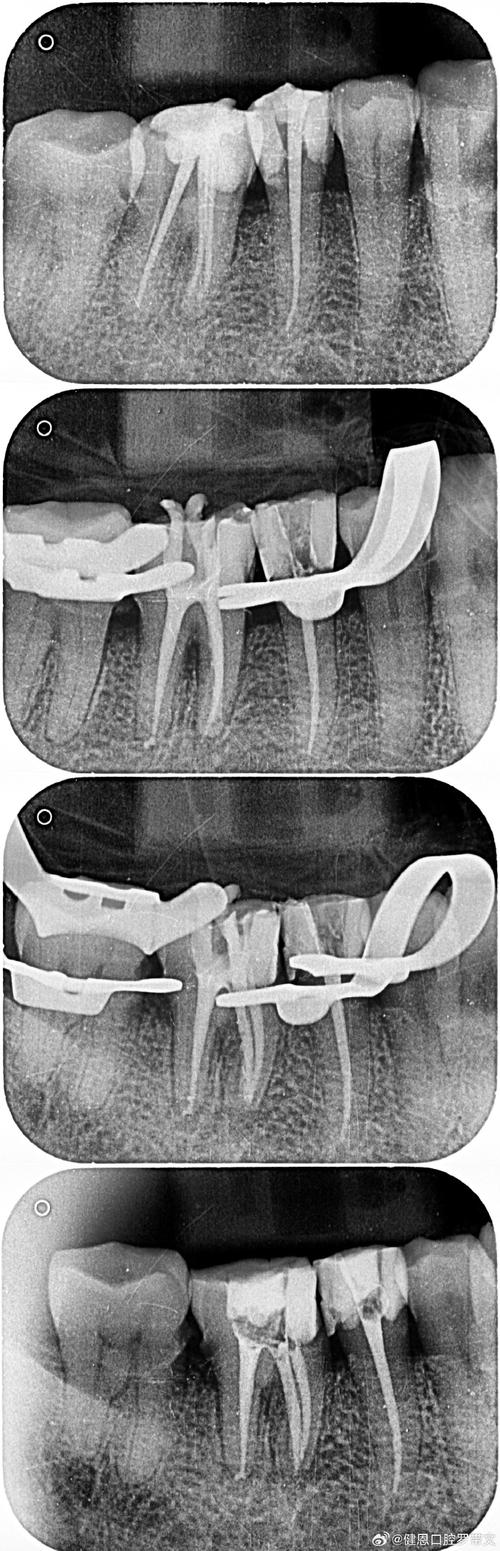

根管钙化是根管治疗中常见的挑战,指根管壁发生矿物质沉积(主要是钙磷化合物),导致根管变细、狭窄甚至完全堵塞,使得常规的根管预备和清洁变得极其困难,处理钙化根管没有单一的“最佳”方法,而是需要根据钙化的具体位置、程度、牙齿位置、医生经验以及设备条件,采用多种技术组合应用,以下是当前公认最有效、最主流的处理策略和关键技术:

(图片来源网络,侵删)- 放大视野: 根管显微镜(牙科手术显微镜)提供高倍放大(通常10-40倍)和良好的照明,是发现钙化根管入口、判断钙化程度、定位钙化物、避免遗漏根管分支和侧副根管的关键。

- 拍摄高质量根尖片、CBCT(锥形束CT,强烈推荐,尤其对于复杂钙化病例,能清晰显示钙化位置、程度、根管数量和形态)。

根管再通与预备:

- 建立通路: 在显微镜直视下,使用小号手动锉(如08号、10号K锉)或超声工作尖配合EDTA冲洗,轻轻探查根管方向,感受阻力,如有阻力,不要强行进入。

- 超声辅助: 使用小号超声工作尖(如C锉、ET40/50),配合大量EDTA冲洗,在根管内轻轻提拉、旋转,利用空化效应和化学作用软化并清除钙化物,逐步向根尖方向推进。

- 镍钛预备: 一旦建立初步通路(通常能通过15号或20号锉),使用小号镍钛旋转器械(如Reciproc R25, ProTaper Next Universal S1, TruNatomy S1)在低扭矩、低转速下进行根管预备,遵循“小号疏通,大号成形”原则,每换大一号器械前充分冲洗。

- 逐步深入: 重复以上步骤,逐步扩大根管,直至到达工作长度(由根尖片或根尖定位仪确定),对于严重钙化或弯曲根管,可能需要多次就诊。

- 严密充填: 使用热牙胶垂直加压技术或连续波技术进行根管充填,确保三维严密封填,钙化根管形态不规则,充填难度大,显微镜下操作有助于确保充填质量。